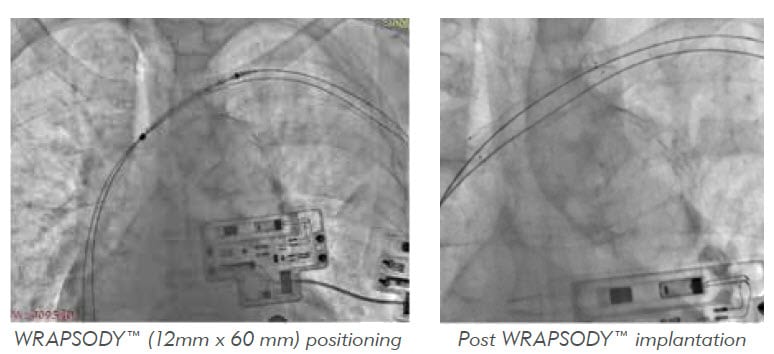

Revisión德卡索2 .

伤口愈合oclusión伤口下静脉复发与WRAPSODY™

Paciente varón de 56 años de edadentratamenento de hemodiálisis durante 5 años con enententenente de ocho程序de静脉成形的前一阶段前一阶段的tratamiento de la estenvia izquierda的静脉复发,brazo的水肿,la cara y el cuello, como se puede ver en la imagen continuación。

RESULTADOS

静脉造影最终结果observó un buen resultado angiográfico并发症。

Se verraron las vaainas, la la止血Se hizo con缝合在烟草bolsa de tabaco在punción de la fístula y compresión在punción de ingle。Se realizó una TAC 7 días después de la implantación, en la que Se observó una WRAPSODY可渗透y bien posicionada, con angulación远端mínima关于al trayecto de la vena sin estenosis相关。